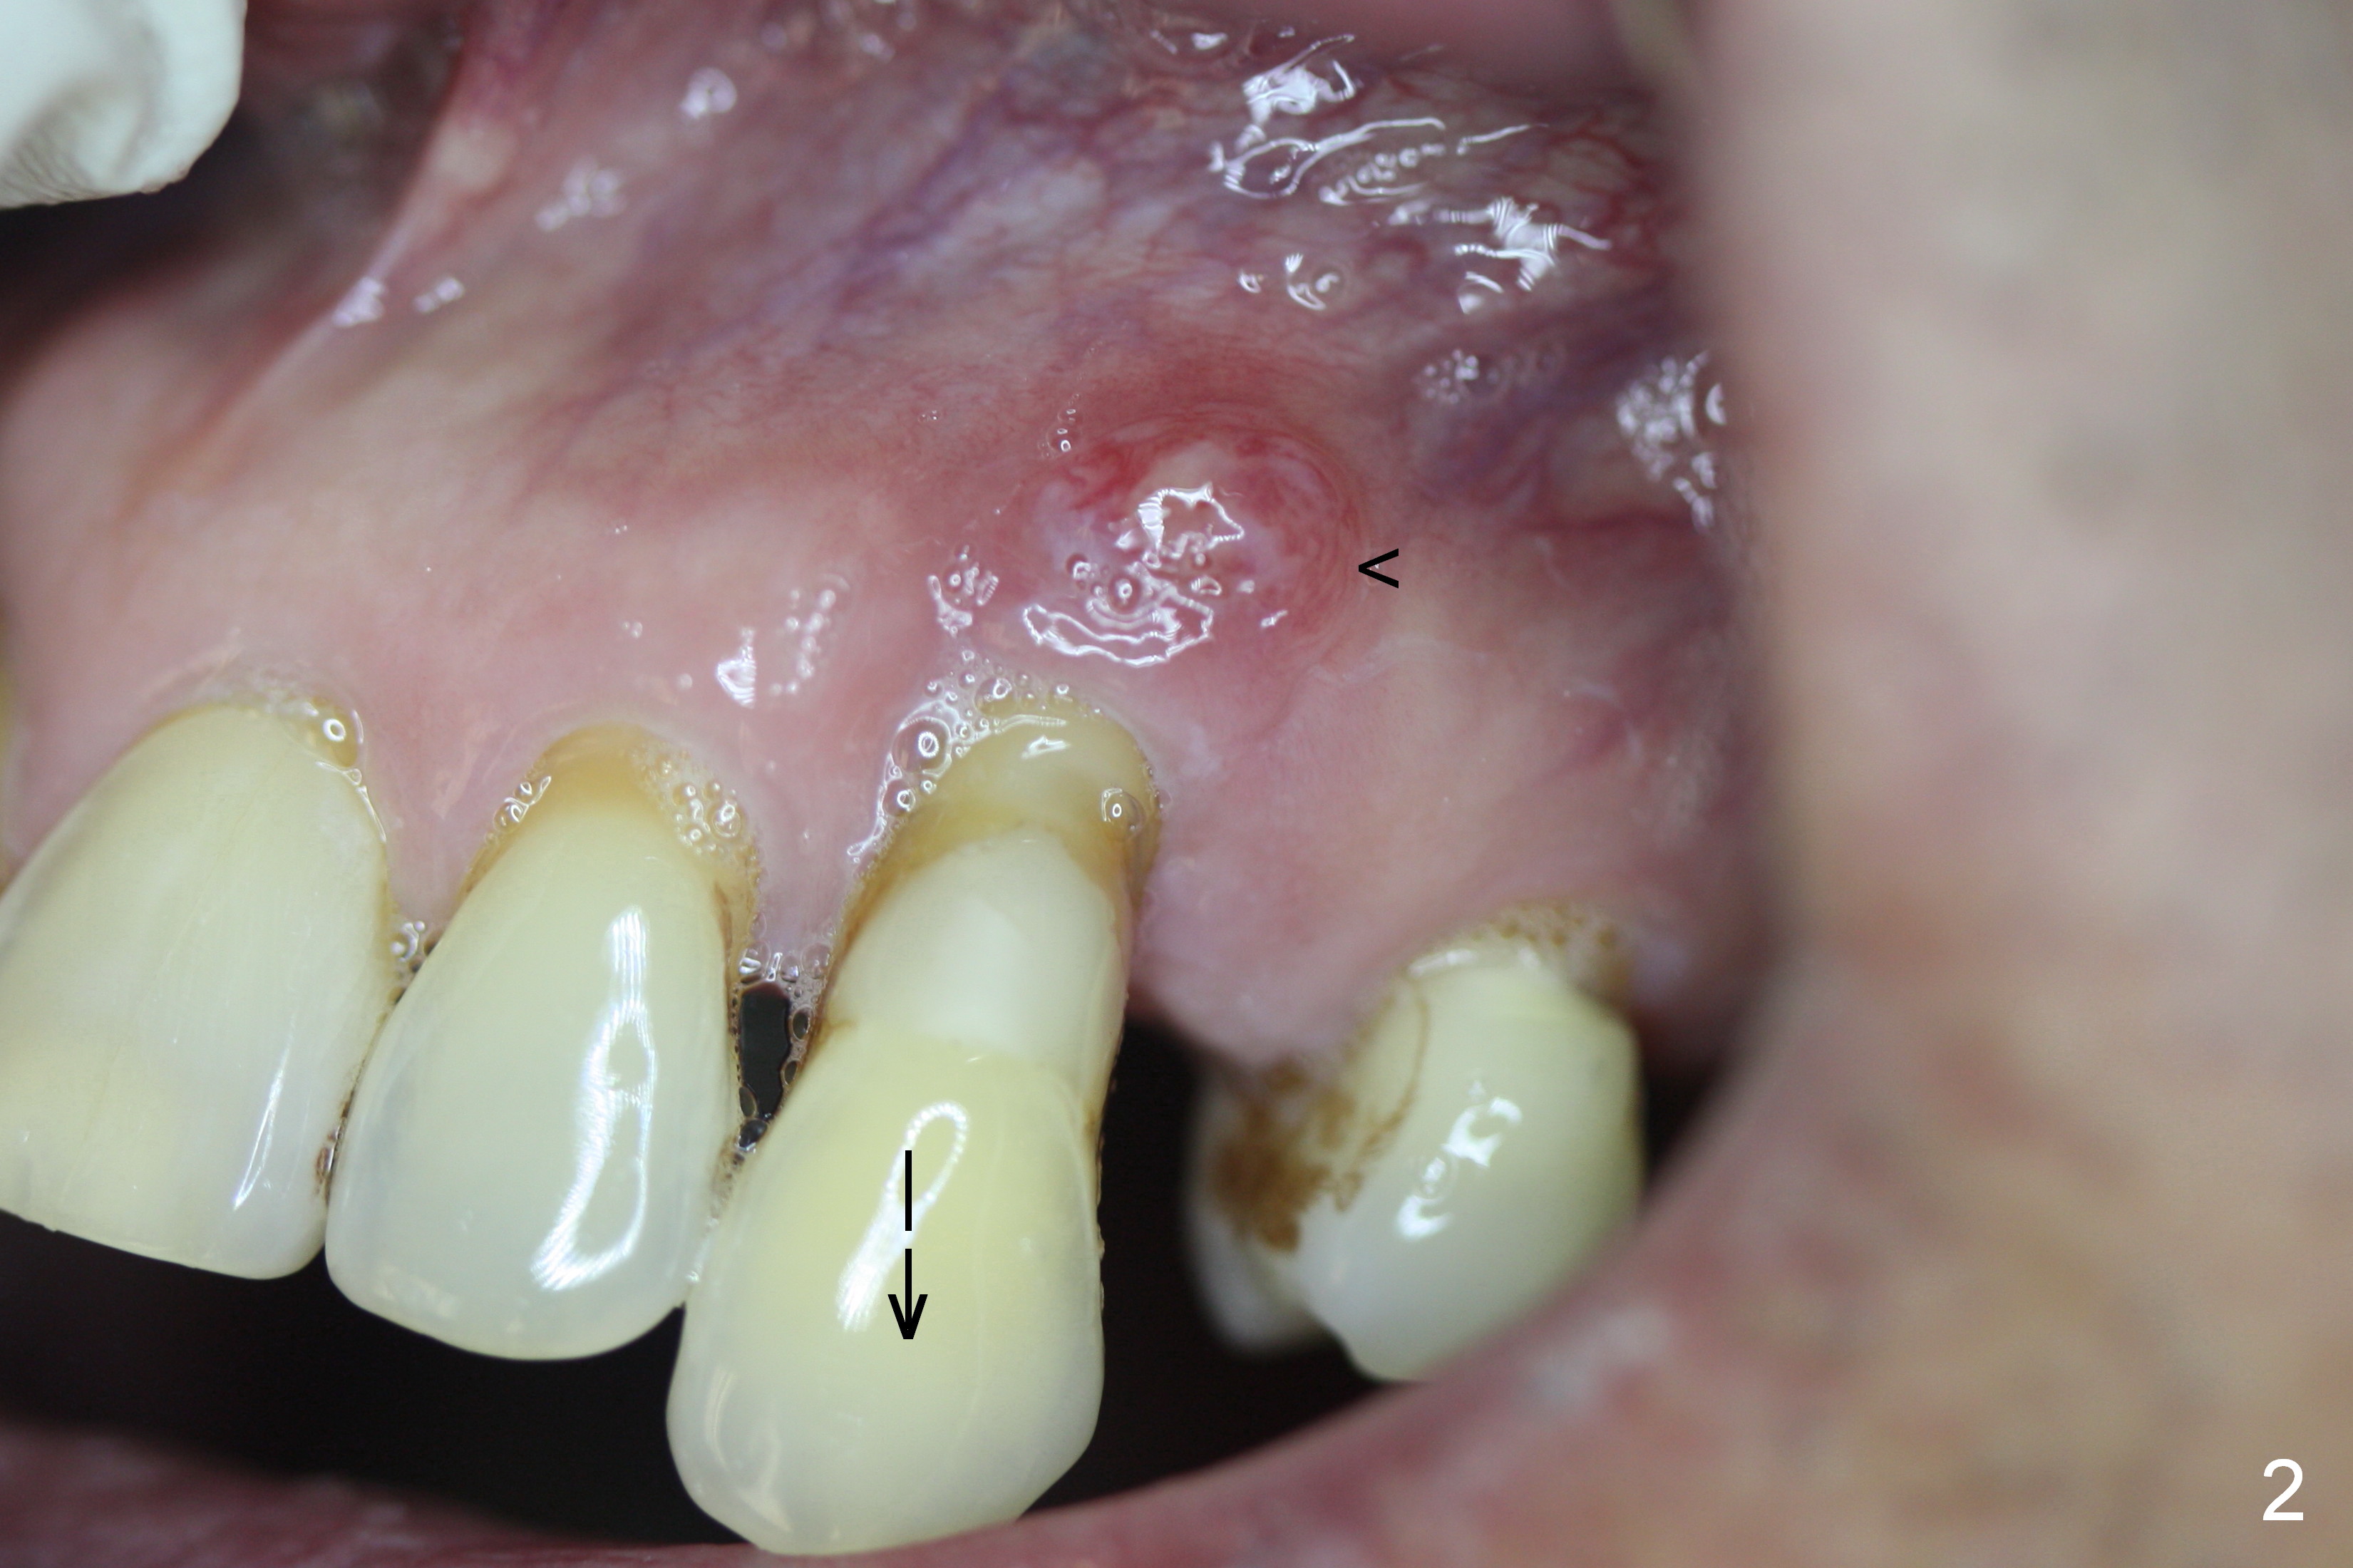

Bone defect at present should be more severe than CBCT coronal (Fig.3) and axial (Fig.4) sections indicate. After palatal placement of a 5x20 mm tissue level implant (Fig.3 green area) and an appropriate abutment, an immediate provisional is to be fabricated. A block graft is harvested from #12 edentulous region (buccal plate) to the buccal defect at the site of #11 (Fig.4 curved light blue arrow). Prepare surgical handpiece and chisels. The remaining bony defect will be filled with allograft and Osteogen (red circles). The graft site is going to be covered by Osteotape (Fig.3,4 pink curved line), while the donor site is given mixture of allograft and Osteogen and Collagen Dressing. When the soft tissue deficiency is found, connective tissue graft is to be harvested from the palate. If visibility is compromised for these steps, an incision will be made as shown in Fig.5. This should be done with caution considering the medical conditions. Before surgery, ask the patient whether the blood thinner has stopped for a few days or not and how diabetes control is.